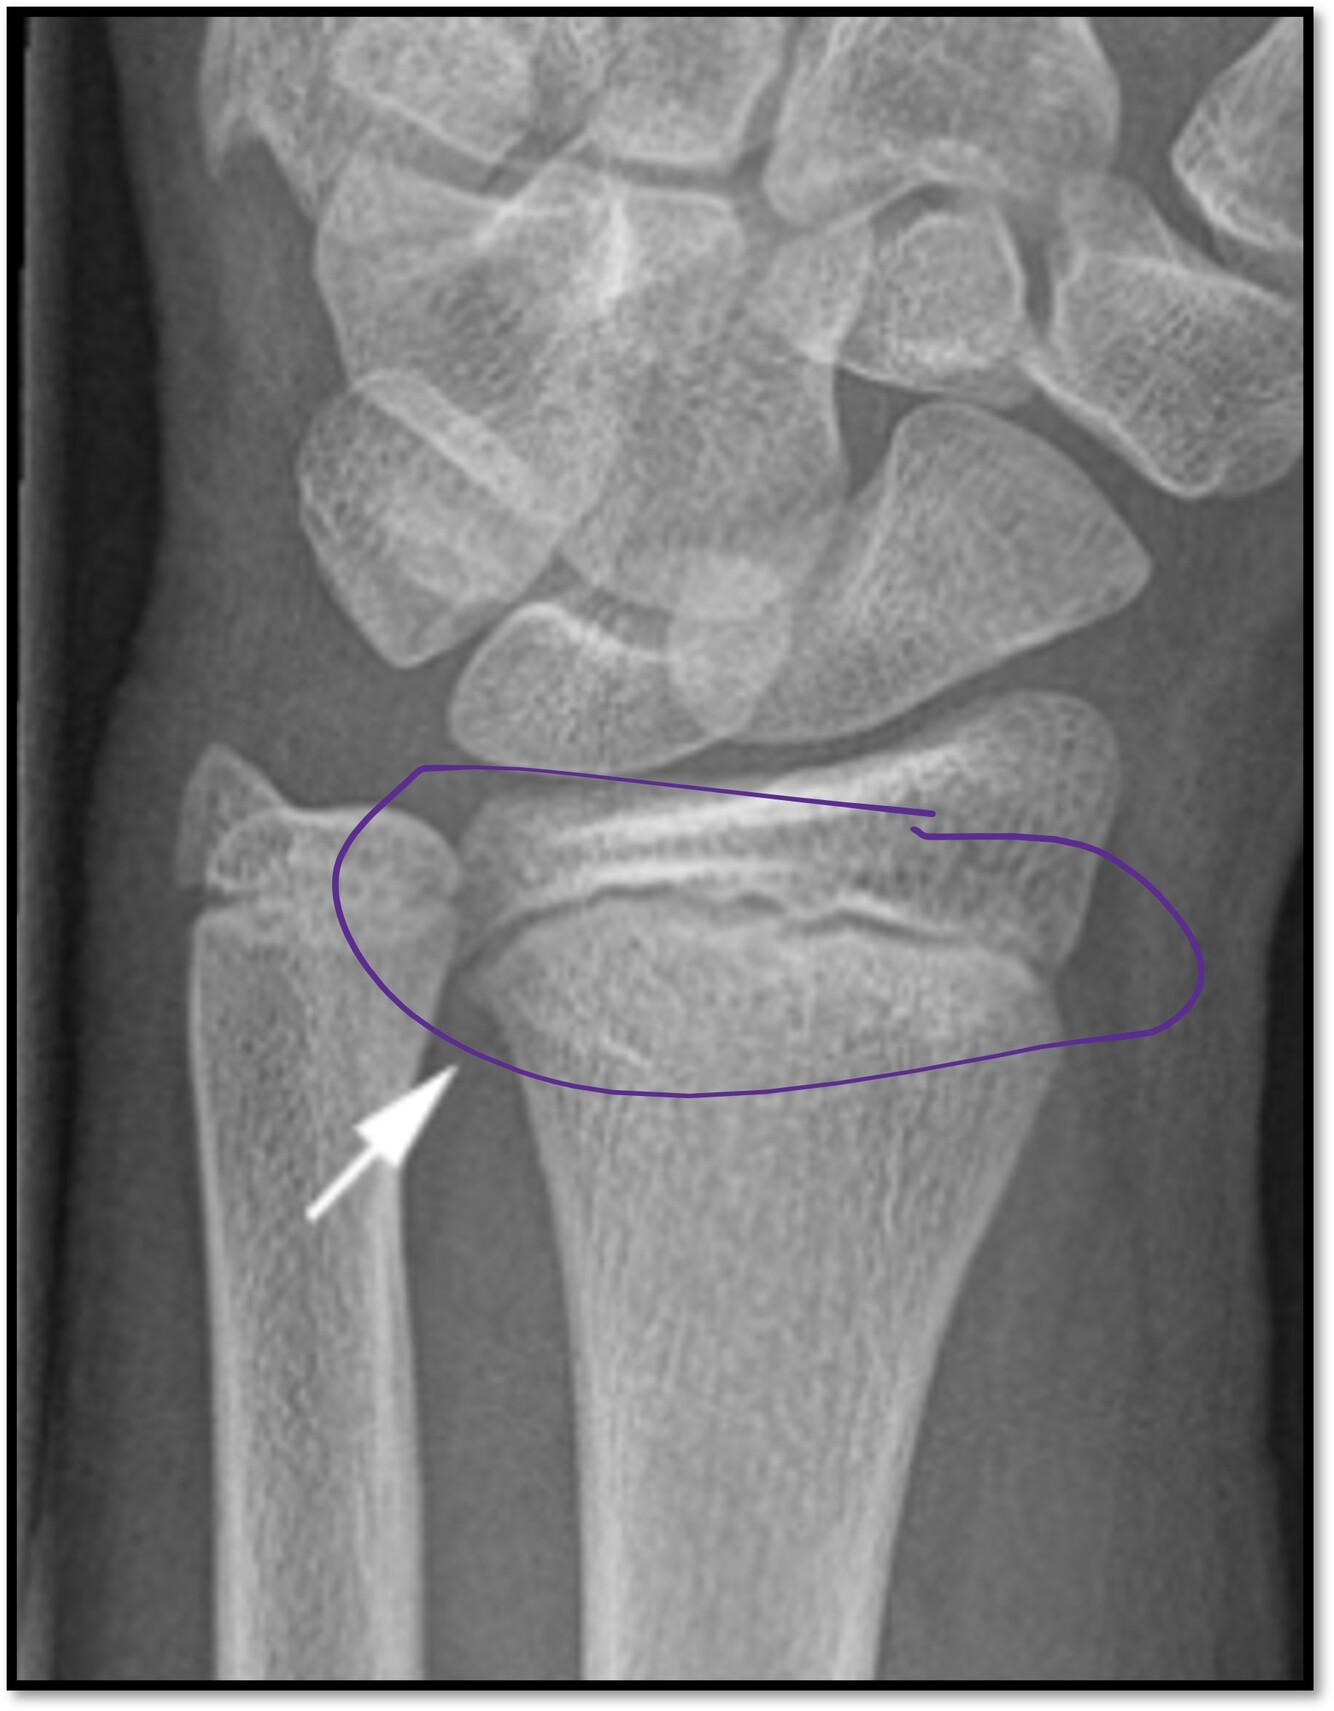

Q

What are the signs that a distal radius fracture is present?

A

Trabecular pattern, lucency, slight posterior angulation and cortical disruption anteriorly

What is circled?

The epiphyseal plate

How well did you know this?